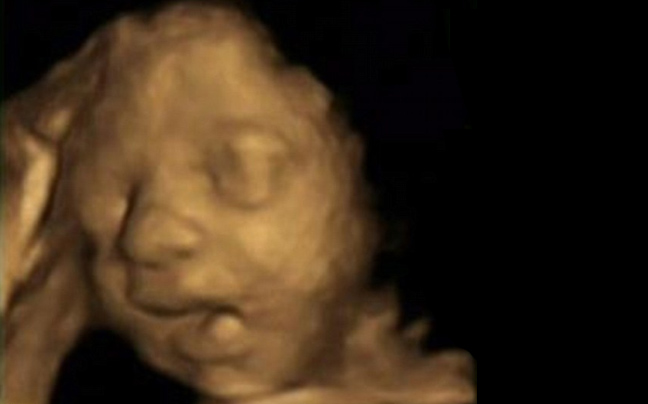

Έμβρυο κάνει στην μήτρα το σήμα της νίκης